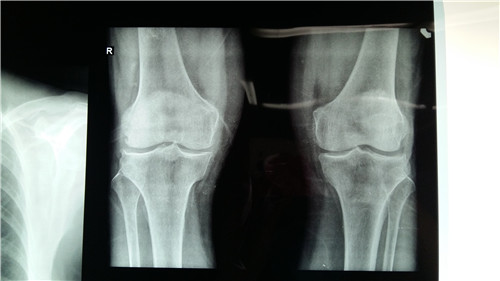

骨性关节炎多发生在人体一些比较大的关节上,如膝关节、腰椎等。而这些关节在平时的活动时比较频繁的,如果有骨性关节炎了,将会造成巨大的影响,所以我们在平时要学会预防骨性关节炎…「查看详情」

骨性关节炎较常见的症状就是关节疼痛,可侵犯软骨组织,而软骨组织具有不可再生的特性,一旦受损严重或者面积过大时,就需要进行人工关节置换手术来保存关节功能了。因此人们在平四做…「查看详情」